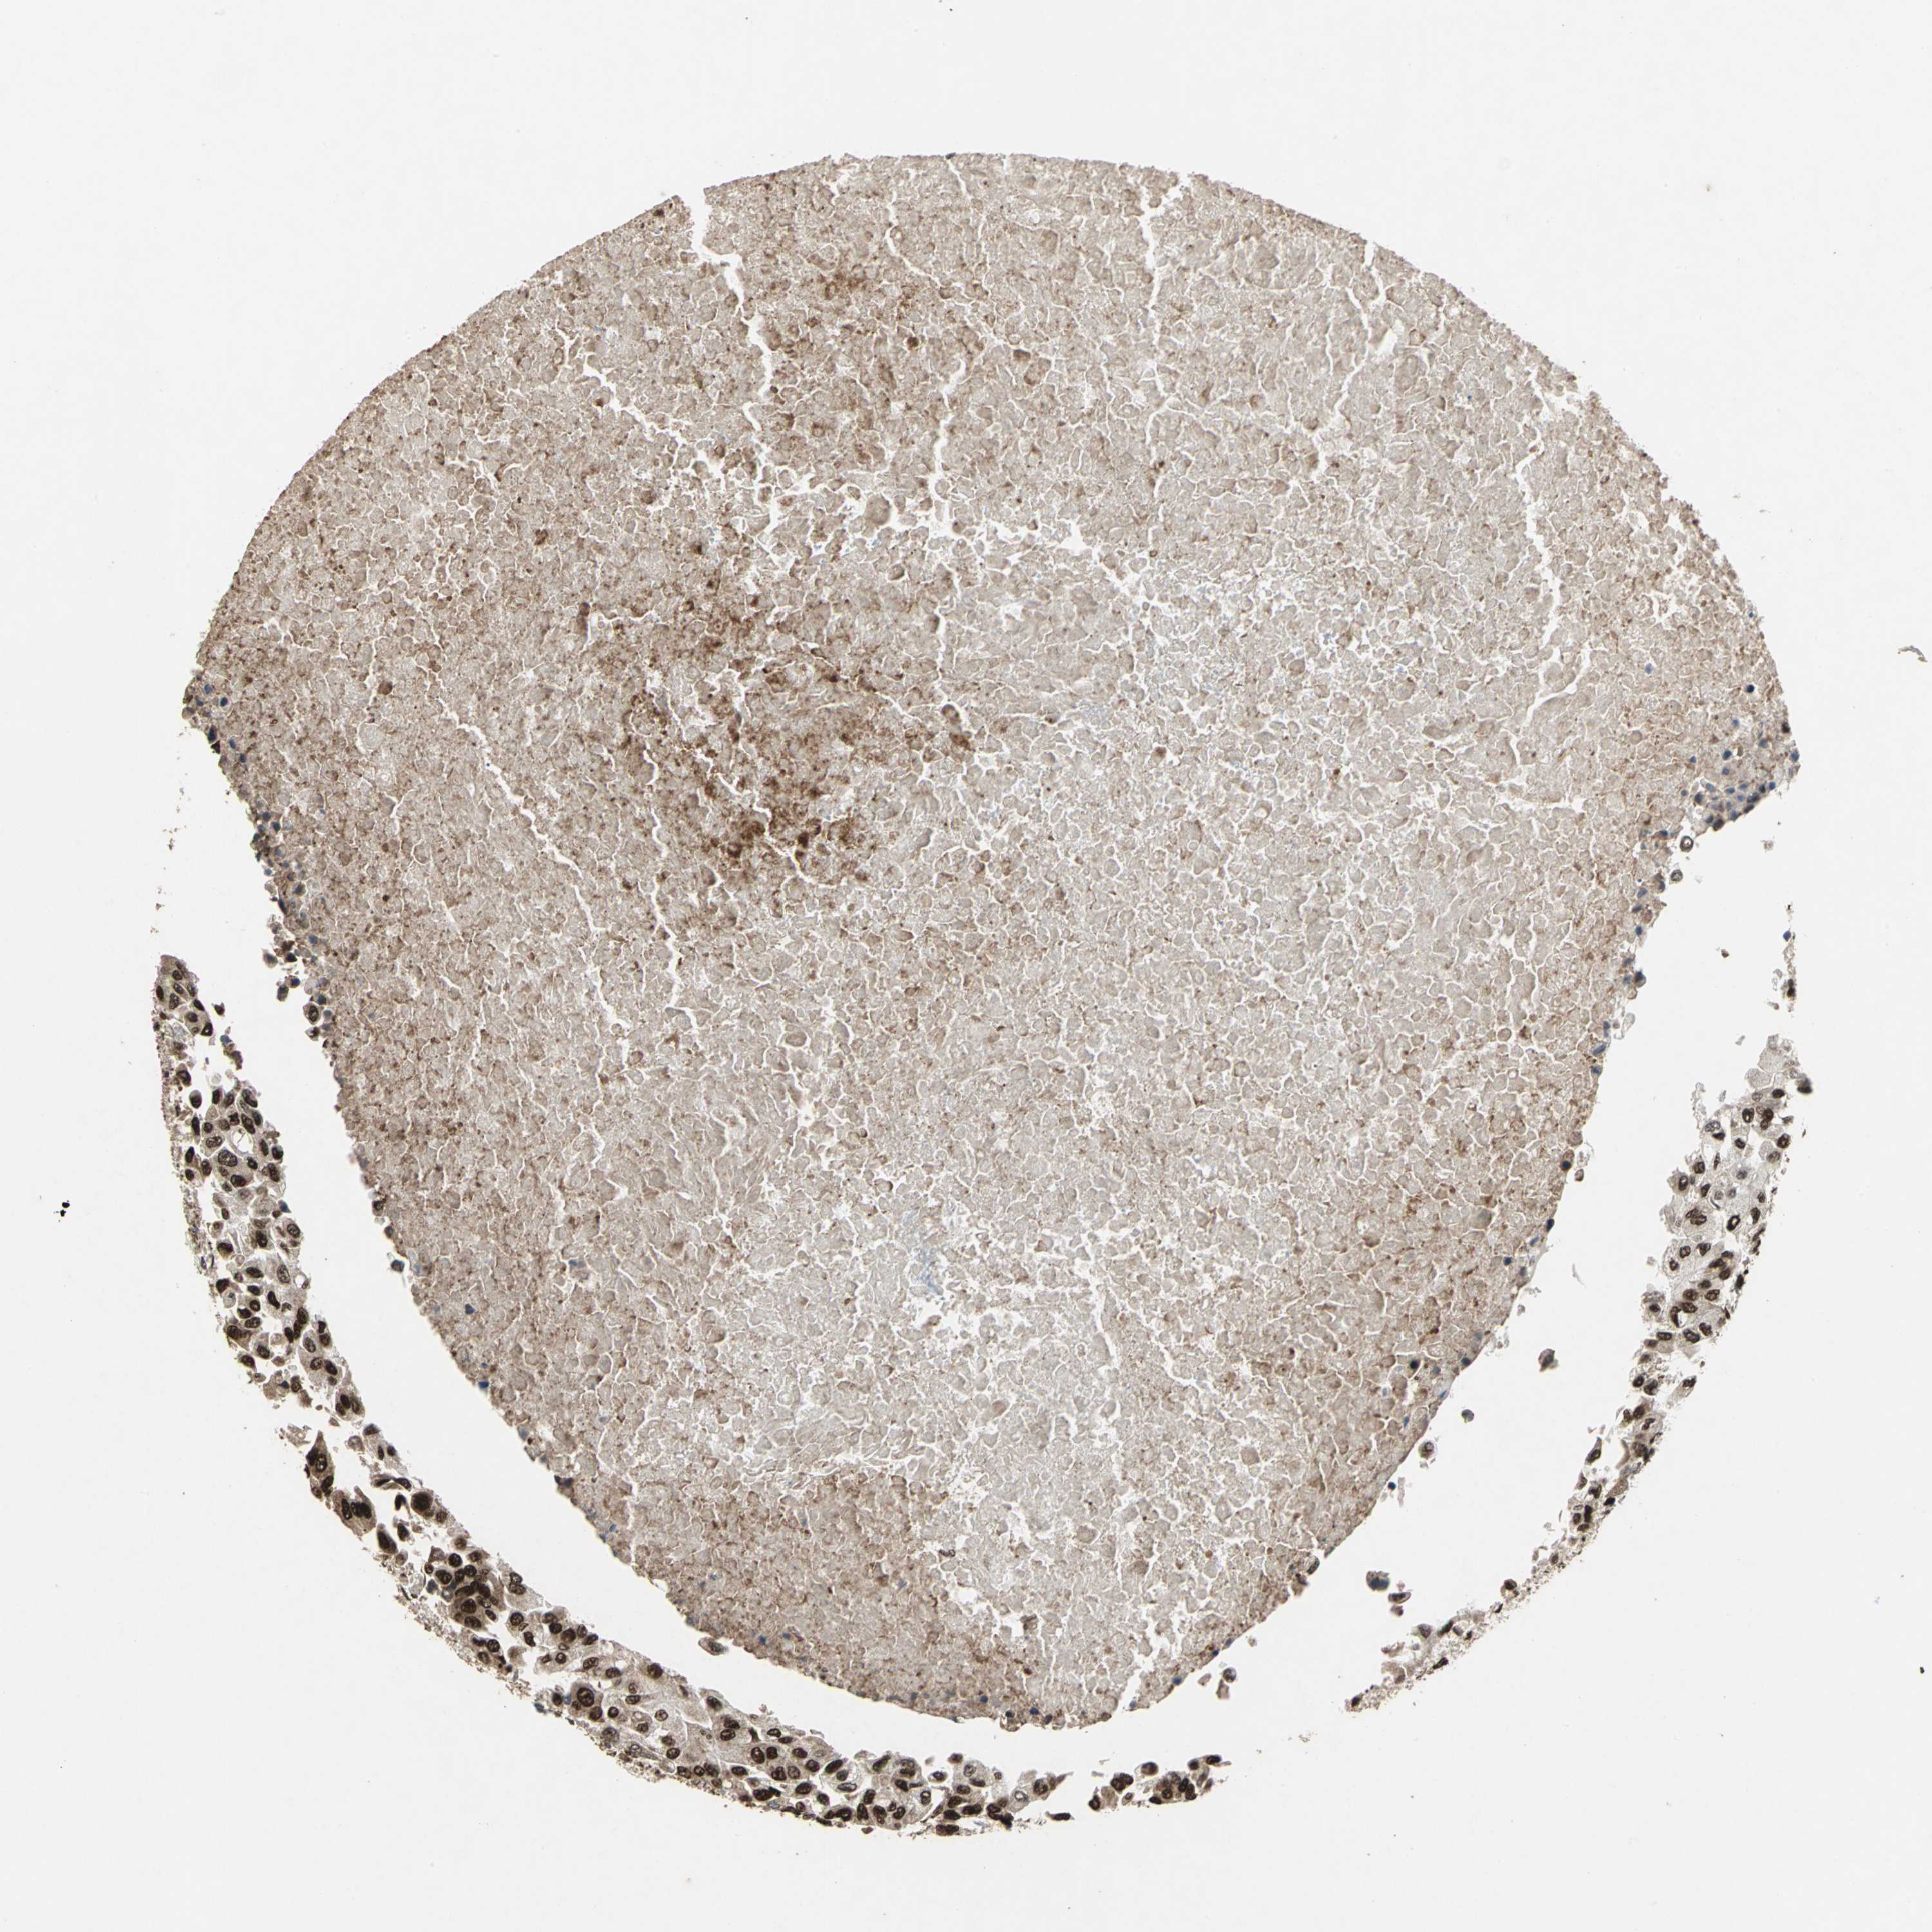

BRCA TCGA BRCA VALIDATION PROTEIN EXPRESSION

Breast cancer

Human cancer